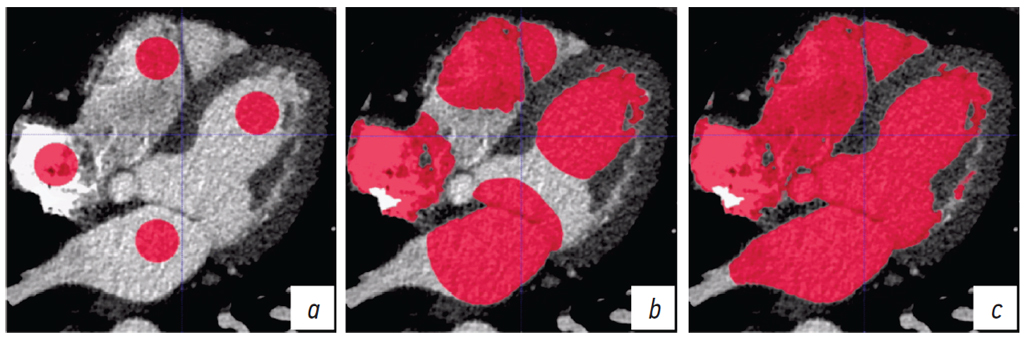

Метод выращивания областей напротив, заключается в поиске среди окружающих заданную область таких пикселей, яркость которых приближена к средней по данной области [16]. Благодаря этому происходит более наглядное, чем при детекции контуров, выделение связной области интереса с меньшей, чем у пороговой обработки, чувствительностью к шуму. Тем не менее, как видно на рис. 3, b, данный метод не учитывает эффект частичного объема — «тонкие» структуры оказались включенными в карту сегментации полостей сердца. Следует также отметить, что данный метод применим для сравнительно крупных сегментов, в которых можно задать начальную область.

Рис. 3. Сегментация полостей сердца методом наращивания областей: а — задание базовых областей; b — избирательное присоединение к базовым областям окружающих пикселей; c — результат сегментации